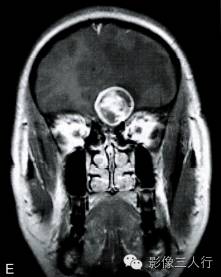

A.T1横断面;B.T2WI横断面;C、D、E~增强横断面、矢状面、冠状面;F.HE×100

图A、B:T1WI、T2WI横断面,图C~E为增强横断、矢状位及冠状位。左额底部见一囊性肿物,囊内见一直径约28mm类圆形肿块,边界清,T2WI呈不均匀高信号为主,内混杂条片状稍低信号,T1WI呈稍低信号,周边见环形稍高信号;增强后病灶大部呈明显强化,内可见不规则无强化区;灶周见液性信号影环绕,并可见大片状不规则水肿,累及左额颞叶、左基底节前部及左侧胼胝体膝部;邻近脑组织受压明显,左侧脑室、右侧脑室前角、3脑室及鞍上池受压变形,前部中线结构右移。